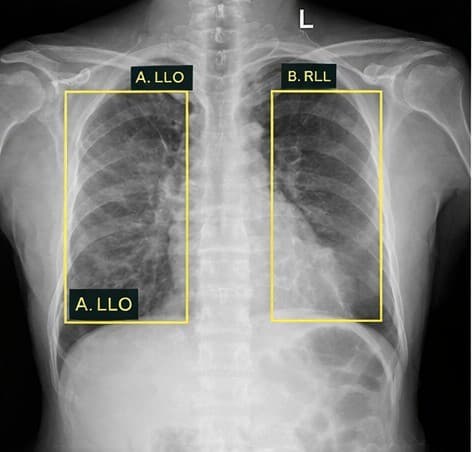

Healthcare Access

Across Africa, millions lack access to quality healthcare. Our AI solutions—from TB and pneumonia detection to telemedicine platforms—are transforming healthcare delivery, enabling faster diagnoses and saving lives in communities that need it most.

AI diagnostic tools, telemedicine platforms, health data analytics, and mobile-first healthcare delivery.